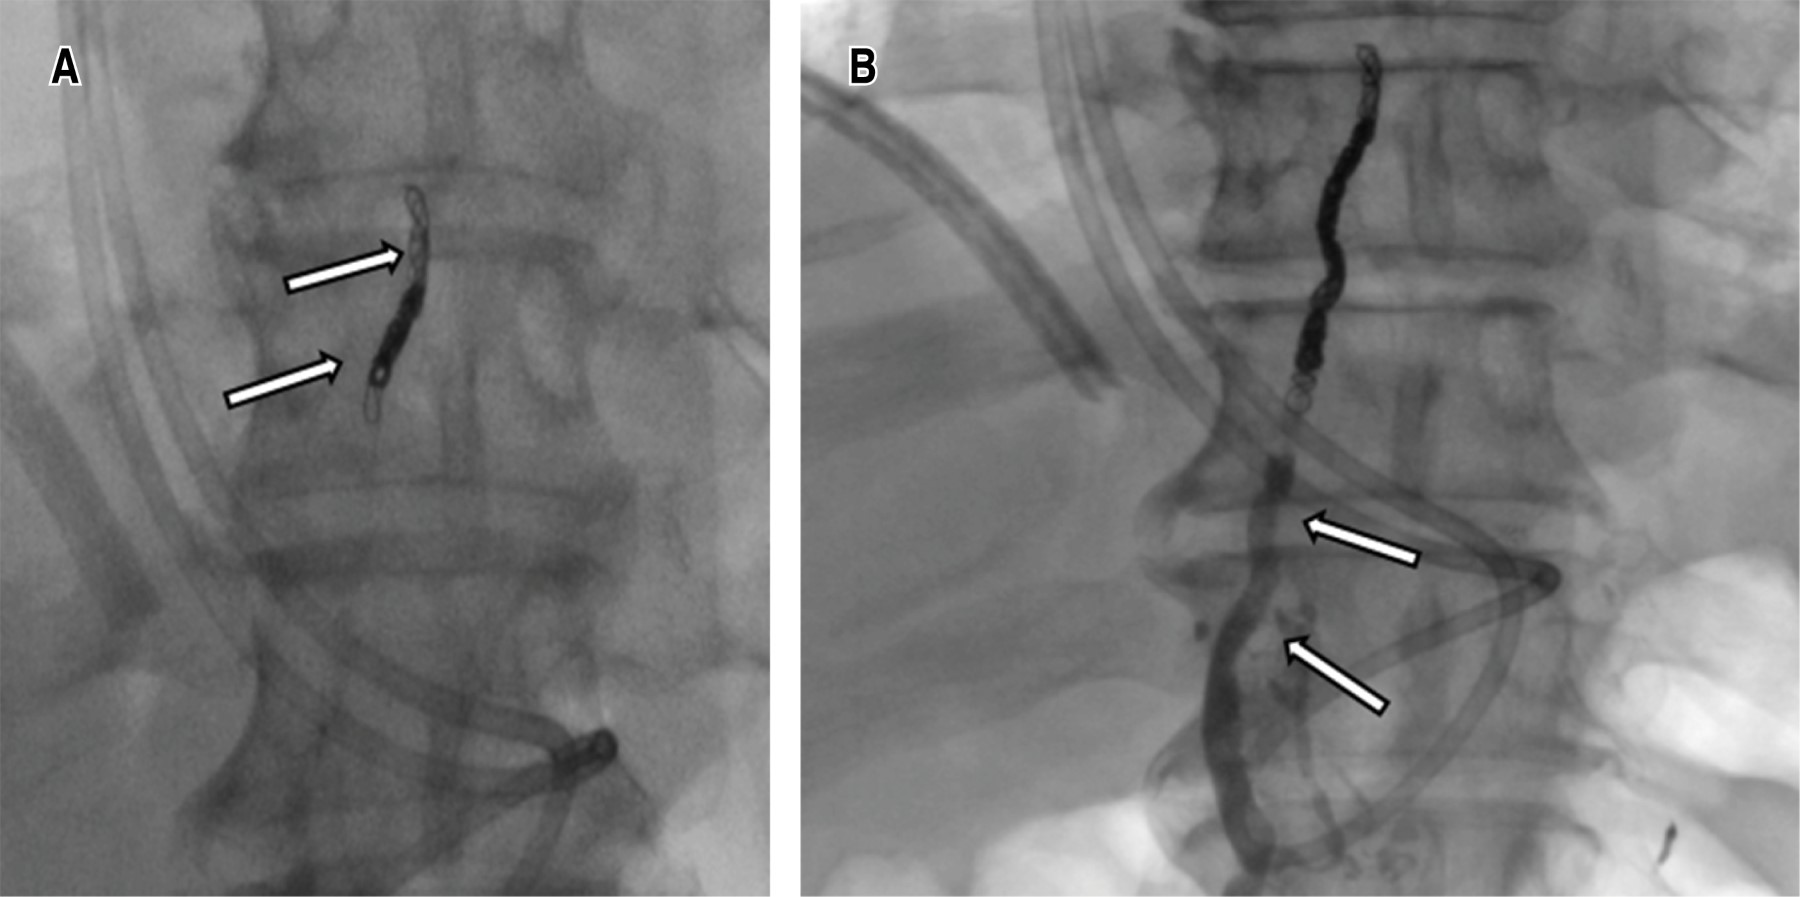

Thoracic duct embolization

Once the chyle cistern was opacified, a disruption of the thoracic duct and contrast leakage into the left pleural cavity was visualized, under fluroscopic control the thoracic duct was catheterized using a 22 G Chiba needle by percutaneous abdominal approach in the epigastric area and with a slightly cranial angulation. Once accessed, a 0.014-inch guidewire was introduced into the thoracic duct and the needle was exchanged for a microcatheter, which was placed as close as possible to the site of the thoracic duct lesion, ideally joining the point of extravasation (Figure 2). Subsequently, it was embolized with microcoils of 2 and 3 mm in diameter proximal to the leak and the embolization was completed with cyanoacrylate. Control ductography showed the resolution of the leak (Figure 3).